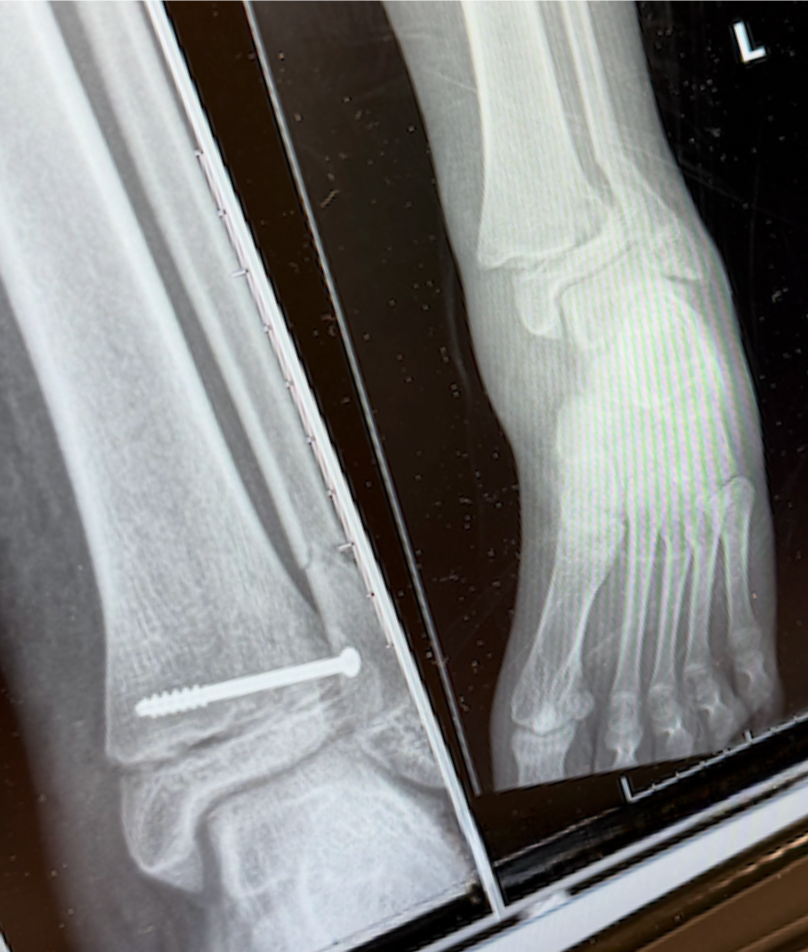

On February 23, Annie’s young daughter, Adelynn, was seriously injured in an accident when another person fell onto her, causing a severe break to her ankle in three places, along with a dislocation and damage to a major artery in her foot which led to compartment syndrome.

What followed was something no family is ever prepared for. Adelynn underwent five surgeries and spent six days in the hospital as doctors worked to stabilize her injury and relieve complications from the trauma.